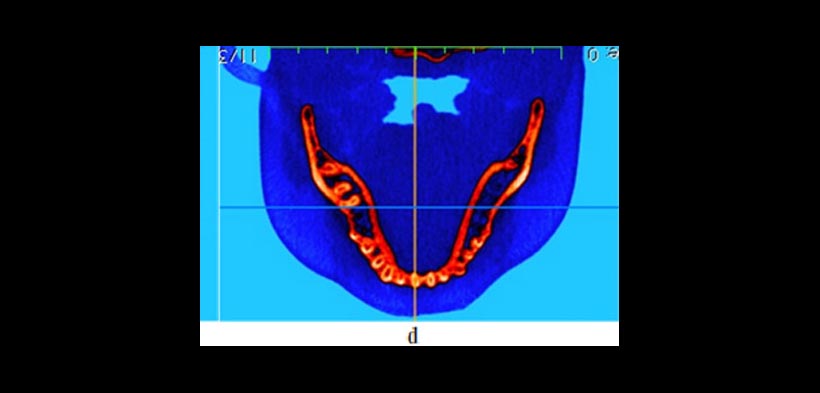

Figura 1. Relación espacial dentoalveolar (A) Una radiografía panorámica ofrece limitado información sobre la localización exacta de los caninos y su relación con las raíces de los incisivos laterales. En contraste, (b) imagen oclusal, (c) frontal y (d) una vista superior de la reconstrucción volumétrica en 3d, muestran la presencia de la reabsorción radicular en ambos incisivos laterales. Estas imágenes también proporcionan importantes Información para el ortodoncsta o cirujano sobre el mejor abordaje.

Figura 2. Uso de la CBCT en el diagnóstico y la planificación del tratamiento de los dientes transpuestos. Un caso que demuestra raíces transpuestas de los caninos superiores y los primeros premolares en la que la CBCT revela que la raíz canina está a vestibular de la raíz premolar. (a) Reconstrucción tridimensional y (b, c) imágenes transversales y la ubicación de la raíz. Todos estos cortes tomográficos pueden ayudar al clínico a optimizar la planificación del tratamiento.

Figura 3. La CBCT ofrece información sobre las condiciones de frontera que no son discernibles a partir de radiografías de rutina o durante el examen clínico, que pueden tener un impacto sobre las opciones de tratamiento. (a) Pre-tratamiento vista coronal que muestra la inclinación lingual (flechas) de los premolares maxilares y la proximidad de sus raíces bucales al margen de la cortical alveolar (puntas de flecha). (b) Post-tratamiento vista coronal que demuestra que las limitaciones ofrecidas por las condiciones de contorno relaciones hueso de la raíz se han abordado mediante torsión lingual de las raíces. (c) vista sagital y (d) vista transversal de la una CBCT de un individuo con limitaciones severas en las condiciones de contorno donde hay ausencia de corticales óseas. El tratamiento de ortodoncia estaría contraindicado en este caso.